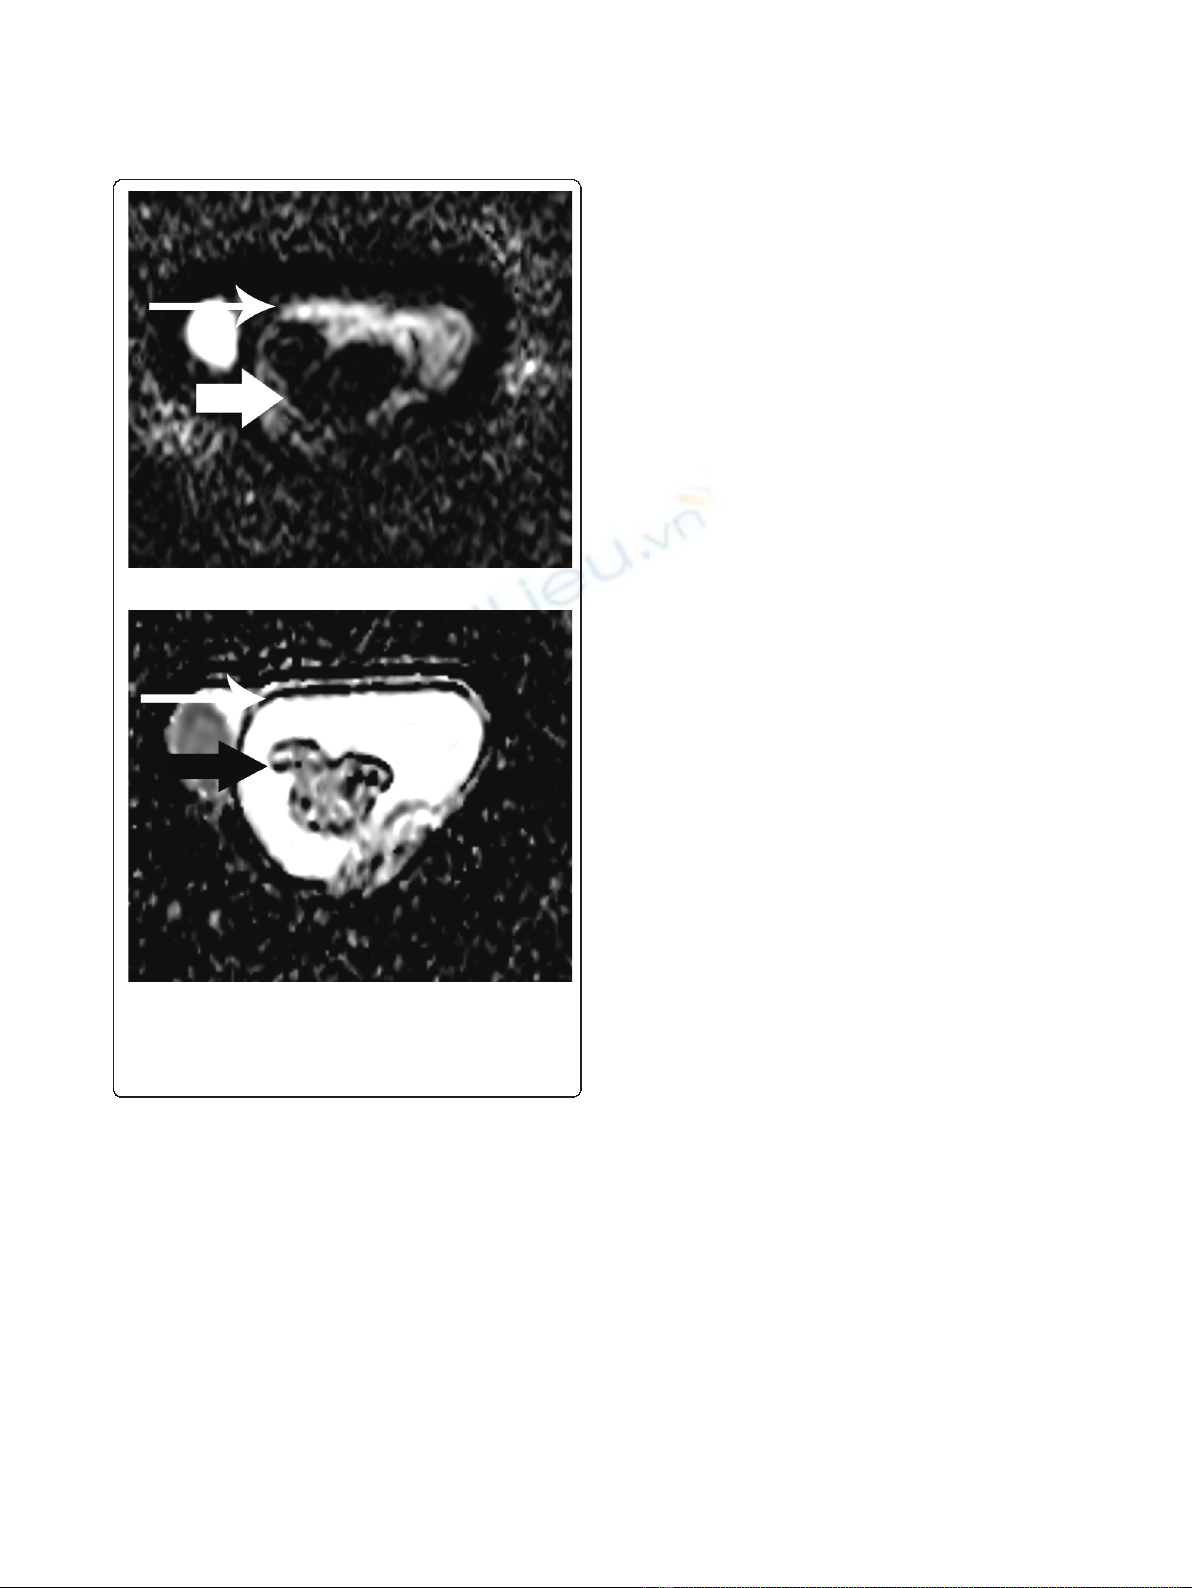

Figure 3 (a) Transverse DW echo planar image (b= 900 mm

2

/

s) and the (b) corresponding ADC map. The mass (arrow)

appears mainly hypointense on DW images, due to the presence of

abundant fibrous part. The ADC value of the fibrous component

was 0.86 × 10

-3

mm

/s. Left hydrocele (long arrow).

MR examination of the scrotum in our patient

revealed the presence of a sharply-demarcated

multilobular paratesticular mass, isointense on T1-

weighted images, heterogeneous, but predominantly of

very low signal intensity on T2-weighted images. One

limitation of the MR protocol used in this study was

that it did not include post-contrast images, although

the lesion was reported with vascularity on sonographic

examination. The hypointensity of the mass on T2-

weighted images and the restricted diffusion on ADC

maps was suggestive for the presence of fibrous tissue,

proved through histology to correspond to the abundant

fibrotic component of an adenomatoid tumor of the